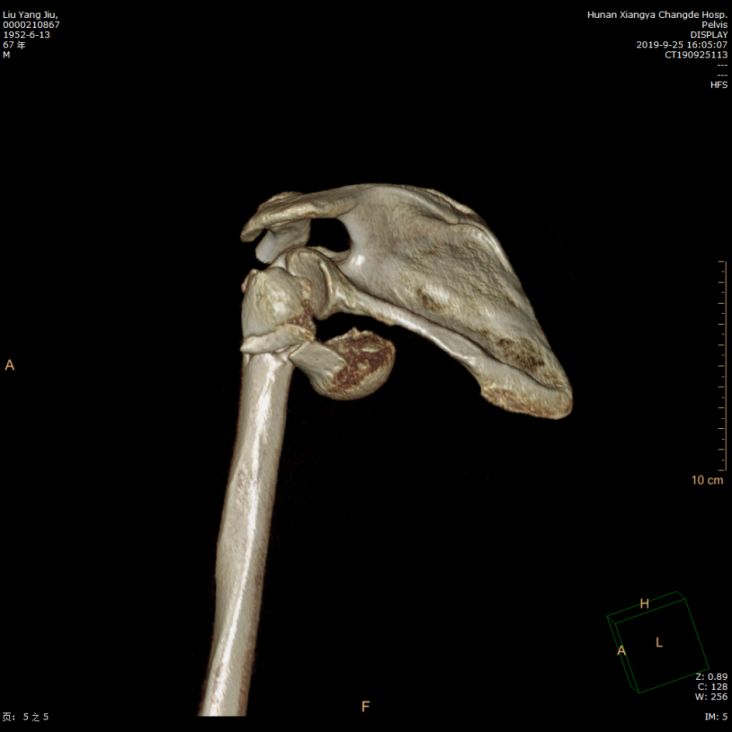

术前左肩关节CT+三维重建,肱骨近端粉碎性骨折

骨科主任张朝跃教授带领的关节外科团队对患者进行详细的病史询问,全面的体格检查及详尽分析临床影像学资料,明确诊断为左肩关节脱位并肱骨近端骨折(Neer四部分骨折),有骨质疏松症,鉴于患者创伤严重,骨折为粉碎型伴有骨质疏松,骨折复位困难,钢板内固定术后肱骨头坏死几率大。张朝跃教授决定行左侧人工肱骨头置换手术,术前与患者及其家属充分沟通,分析手术的必要性、适应症以及肩关节置换手术治疗安全、恢复快,可以改善肩关节功能等特点,刘爷爷及其家属充分理解并决定行该手术治疗。